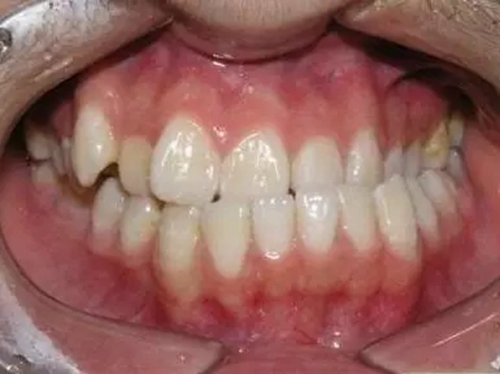

1、錯(cuò)合畸形、咬合關(guān)系紊亂

由于反復(fù)向一側(cè)運(yùn)動(dòng),使下前牙的正中線向一側(cè)錯(cuò)位從而導(dǎo)致后邊的牙齒形成刃對(duì)刃、尖對(duì)尖的咬合,甚至反咬合(下牙包上牙)。

2、導(dǎo)致大小臉

總是固定用一側(cè),該咀嚼側(cè)經(jīng)常得到鍛煉,促進(jìn)了頜骨及肌肉的發(fā)育,因而該側(cè)面部組織豐滿。經(jīng)常不用或少用的那一側(cè)因缺乏鍛煉使面部組織發(fā)育較差、萎縮變小,從而造成發(fā)育不對(duì)稱(chēng),一邊臉大,一邊臉小。